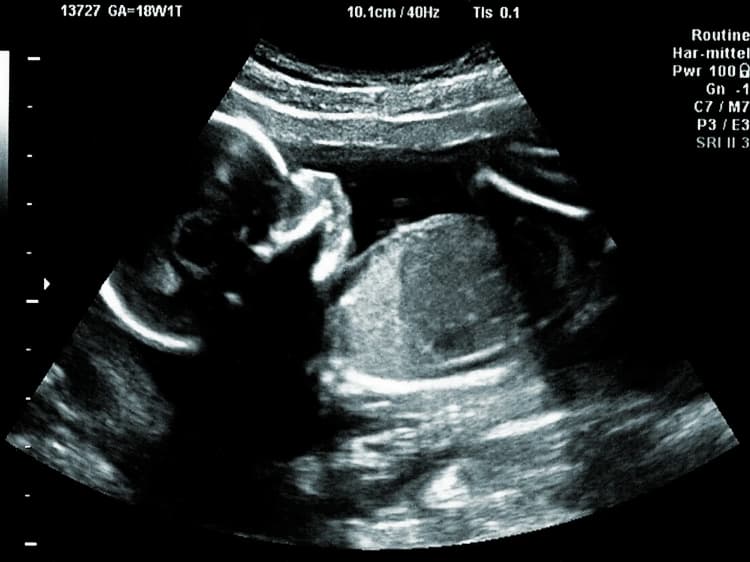

Understanding pregnancy weeks and trimesters can help you track the progress of your pregnancy and anticipate key milestones and developments for you and your baby. Each week and trimester represents distinct stages of growth and milestones in your pregnancy journey.

Each stage of pregnancy is a profound and transformative experience. From the very beginning to the moment you welcome your newborn, each week brings its own special changes as both your baby and your body grow and evolve.